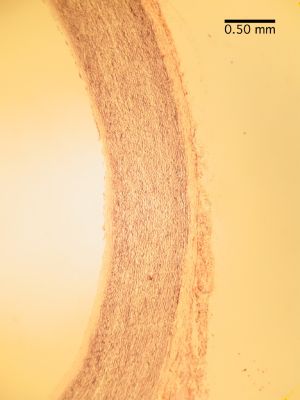

Aorta - histology slide

This is a histology slide of the aorta. 400X total magnification.

Histology slide courtesy of William L. Todt, Ph.D. at Concordia College, Moorhead, Minnesota.